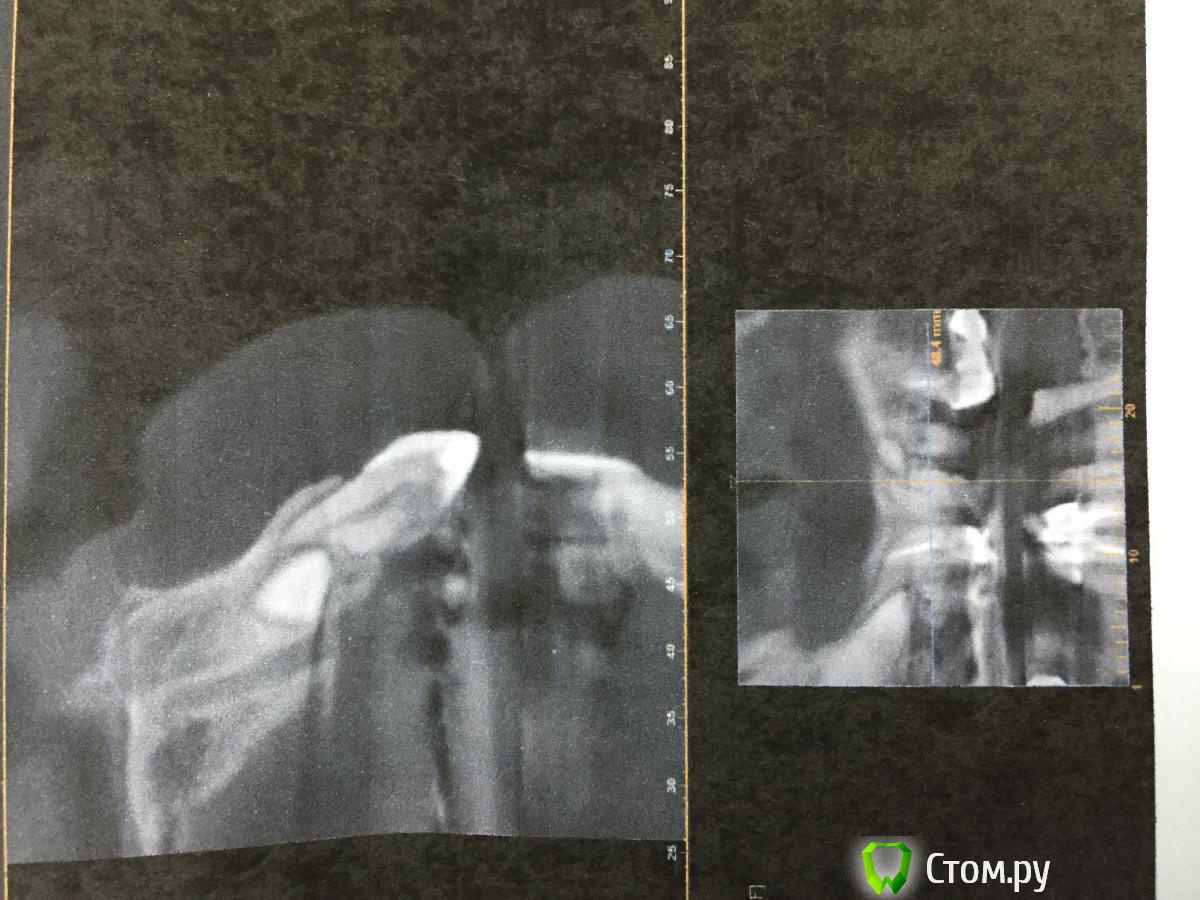

Opimar Опубликовано 18 ноября, 2014 Поделиться Опубликовано 18 ноября, 2014 Здравствуйте. Вот как мне кажется интересный случай. Пациентка 57 лет. На верхней челюсти одиночные 21,22. Мост на 11 и 12. Жалобы на подвижность и боли в области 11,12. На ОПТГ обнаружена ретенция, дистопия 13,23. Была направлена к терапевту для перелечивания 11,12,21 и 22. В процессе работы у терапевта возникли сомнения по поводу состоятельности корней зубов. Направлена на КТ. На КТ резорбция корней на 1/2 из-за клыков. Принято решение об удалении 11,12,21,22, ретенированных 13 и 23 с последующей костной пластикой и имплантацией через 6мес. Собственно сегодня выполнен первый этап: 1. Удалил 11,12,21,22 2. Трапецивидный лоскут от 11-22. 3. С помощью бор машины выпиливание 23 с разделением зуба на 2 фрагмента. 4.кюретаж лунки5.мобилизация лоскута6.заполнение лунки 23 Osteobiol mp3, сверху мембрана Evolution 7.фиксация лоскута Vicryl 4-0, Корален 4-0.Холод на область операции, антибиотикопрофилактику начали еще вчера.Удаление уложилось в 1.5 часа+ 30 мин подсадка и швы. Теперь вот думаю когда заниматься 13 и стоит ли? Может попытаться имплантанты мимо него поставить? Спасибо. Ссылка на комментарий

Opimar Опубликовано 19 ноября, 2014 Автор Поделиться Опубликовано 19 ноября, 2014 5 карпул это сильно. А какая анестезия проводилась вами для данного. Вмешательства ?Зуб был развернут коронкой от 21-22 вглубину челюсти к 24. Инфильтрация с вестибулярной стороны и небная анестезия на протяжении клыка. Ссылка на комментарий